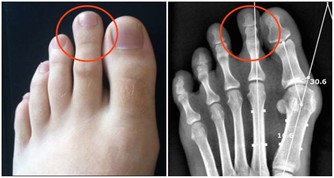

晨起後開始活動,長時間行走,劇烈運動或久坐起立開始走時膝關節疼痛僵硬,稍活動後好轉,上、下樓困難,下樓時膝關節發軟,易摔倒。蹲起時疼痛,僵硬,嚴重時,關節酸痛脹痛,跛行,關節功能受限,以下蹲最為明顯,伸屈活動有彈響聲,部分患者可見關節積液,局部有明顯腫脹、壓痛現象,合併風濕病者關節紅腫、畸形。